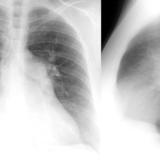

ASD 1 Lat

Date: 03/17/2004

Views: 2492

ASD 1 PA&Lat

Views: 3067